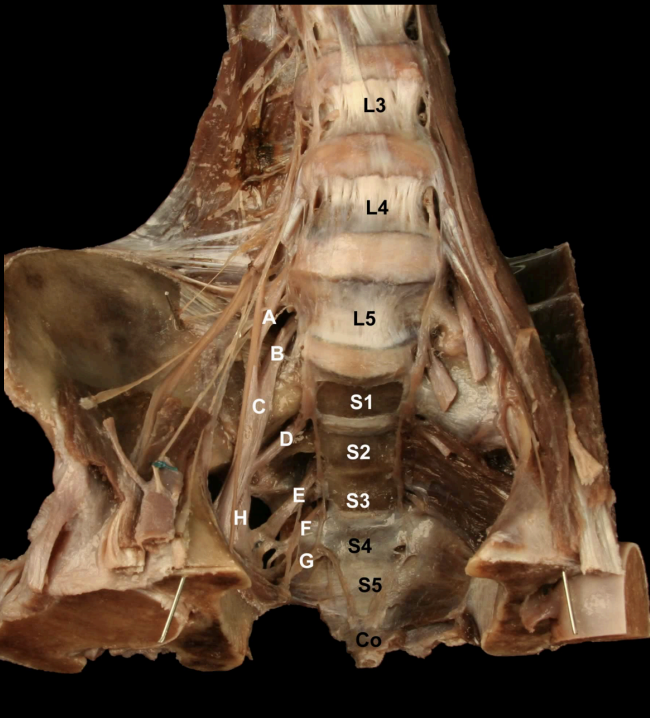

<p><strong>&nbsp;</strong></p><p>Identify the Nerves and their corresponding nerve levels indicated on this <strong>Anterior view</strong> of the Pelvis:<strong> Sacral Plexus</strong></p>

Identify the Nerves and their corresponding nerve levels indicated on this Anterior view of the Pelvis: Sacral Plexus

A. L4 Nerve Root

B: L5 Nerve Root

C: Lumbosacral Trunk (L4-L5)

D: S1 Nerve Root

E: S2 Nerve Root

F: S3 Nerve Root

G: S4 Nerve Root

H: Sciatic n. (L4-S3)